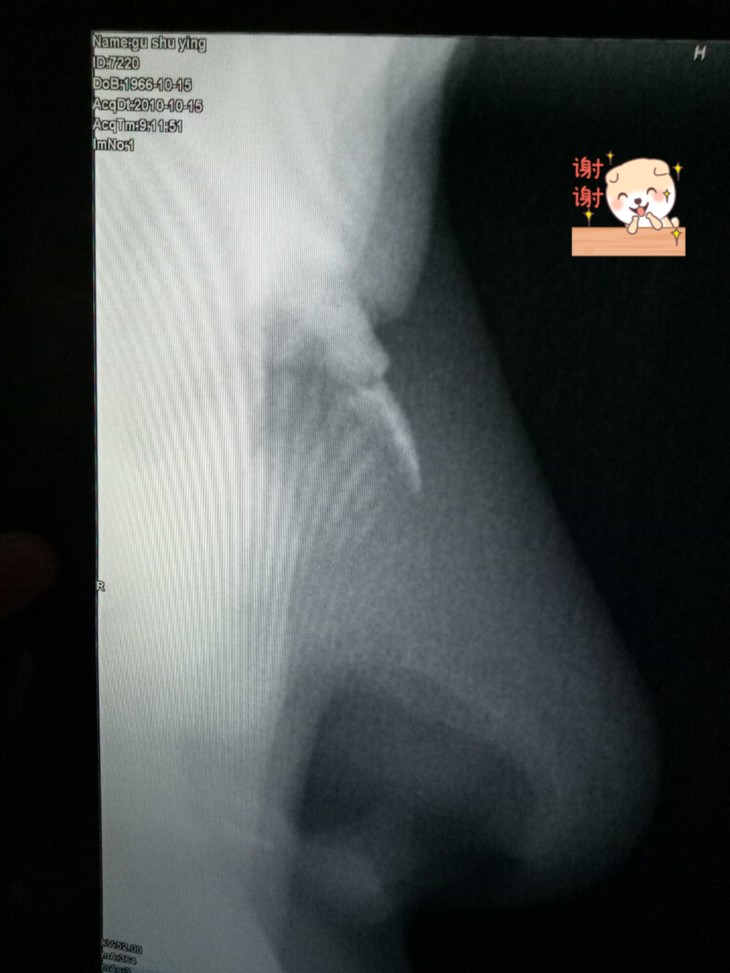

2010年鼻骨骨折X光片子和报告

三、5月4日,第六天:喷姜粉时用力太大了,因为失误喷多了,辣得很难过,鼻子很疼,辣的流出那么多眼泪,而且头顶两侧就像抽筋一样疼,疼了几分钟(小孩和老人慎用,可以用姜汤和姜粉泥喷)。令人惊奇的是,我九年前鼻骨骨折后,鼻子一侧不通气竟然在三个多小时以后通气了。其实也不是一次就康复了,是因为已经喷了几天了,虽然前几次没有太大的感受,也奠定了基础,加上这一次给了大量的热量,就复原了。因为了解原始点原理,也没有紧张;还劝自己,一次或者几次喷姜粉辣的痛苦,可以替代病苦折磨几年,甚至终生,还是值得的,一定要挺住,念力很重要。自己胸闷好几年了,可能是鼻子不通气的原因,呼吸不通畅引起。更神奇的是,第二天早晨起床,觉得喘气不费劲了,胸部很轻松,呼吸通畅的感觉真好。也许鼻腔通畅了,呼吸顺利了,氧份代谢也提高了,心情明朗很多。第一次喷很辣,一旦突破了,再喷多也没有那么辣了。这次大量喷姜粉辣得很痛苦,半小时后我就是忍不住了,就把姜粉都擤[xǐng]鼻涕擤出来了,同时眼睛的泪道带出来很多黏糊糊的分泌物,否则若姜粉停留时间长些效果会更好。既然这么好,就迫不及待的给我先生的鼻腔和喉咙喷了姜粉,只喷4次,20年的鼻炎基本痊愈。先生最后一次也是给鼻子误喷多了姜粉,辣的眼泪哗哗流,第二天鼻炎就好了,吐痰也少了,真没想到效果那么好。喷姜粉的初衷是调理嗓子不疼,没有别的希望,没想到带来这么多惊喜!!!